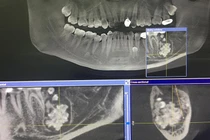

Bệnh viện đa khoa Hùng Vương (tỉnh Phú Thọ) ngày 4/19 cho biết các bác sĩ tại đây vừa phẫu thuật thành công một ca u răng, lấy ra gần 20 chiếc răng trong khối u cho bệnh nhi 12 tuổi. Bệnh nhi được gia đình đưa đến bệnh viện khám với lý do 12 tuổi nhưng răng nanh hàm trên bên trái vẫn chưa mọc. Kết quả chụp X-quang răng của bệnh nhi cho thấy hình ảnh khối u răng kết hợp vị trí hàm trên bên trái.

| Khối u răng qua hình ảnh X-quang răng toàn cảnh. Ảnh: BVCC. |

Các bác sĩ chỉ định phẫu thuật loại bỏ khối u răng. Khối u răng được loại bỏ với gần 20 chiếc răng nhỏ li ti nằm trong khối u có đầy đủ thân răng, tủy răng, chân răng. Sau khi loại bỏ khối u, các bác sĩ đã thực hiện đặt khí cụ kéo răng nanh ngầm về đúng vị trí. Hiện sức khỏe của bệnh nhân đã ổn định và có thể ra viện.